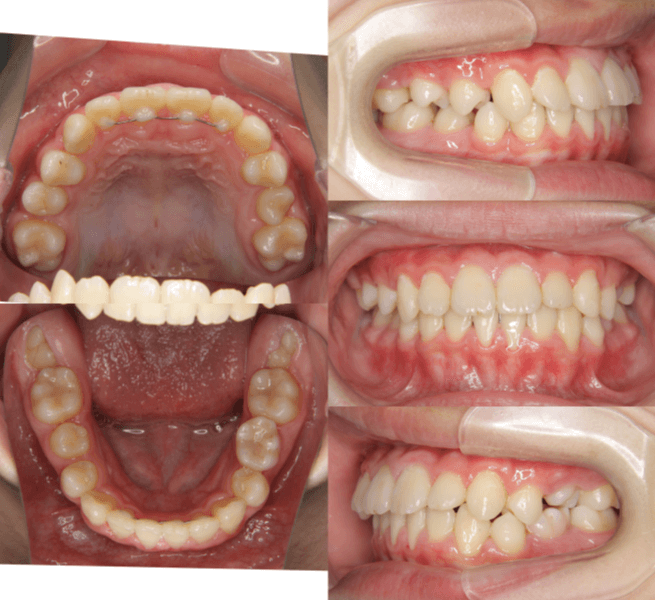

| 年齢・性別 | 11歳1ヶ月の女性 |

|---|---|

| 主訴 | 口元の突出感と歯並びが気になり、将来的な咬合状態を整える目的で来院された患者様です。 |

| 治療期間・回数 | 2年6ヶ月・25回 |

| 費用 | 720,000円 |